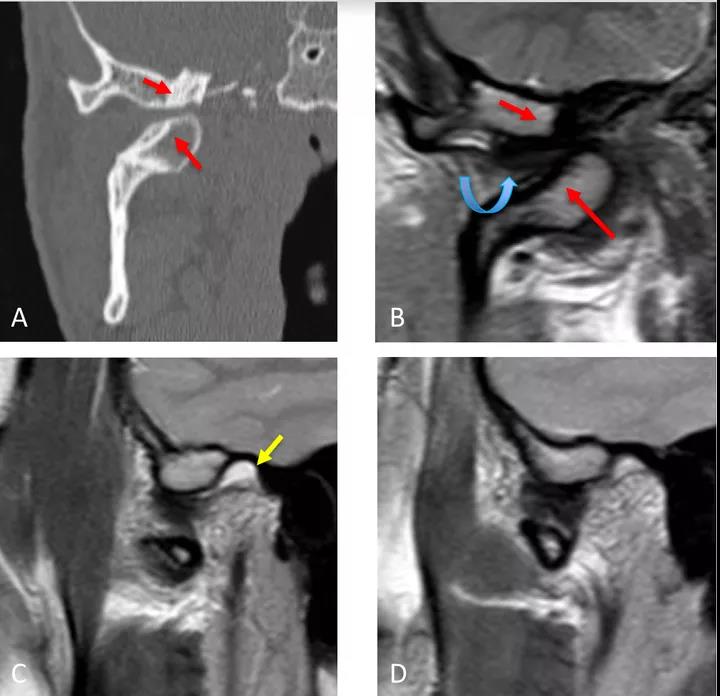

冠狀面CT圖(A)和冠狀面PDWI圖(閉口)(B):顯示由于先前骨折導致的下頜髁突內側移位的顳下頜關節脫位,與骨折畸形愈合、前上髁和后顳嵴硬化(紅色箭頭)相關。關節盤位于下頜骨髁突和顳突之間,失去正常的形態(彎曲箭頭)。

矢狀位T2WI圖(閉口)(C):顯示正常位置的下頜骨髁突及關節積液(黃色箭頭)。

矢狀位PDWI圖(開口)(D)顯示髁突明顯偏移。